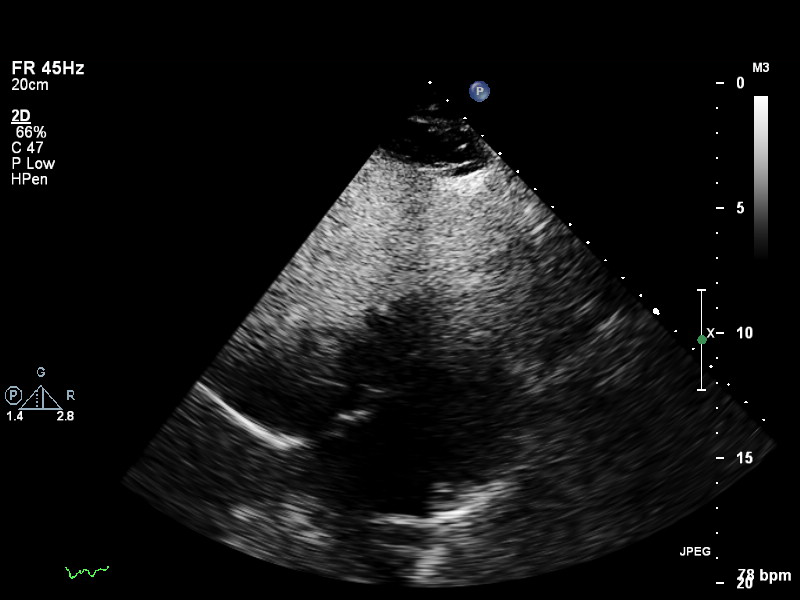

a4ch-full a4ch-full Apical 4-chamber showing the full depth of all four chambers (no LV/RV focus)